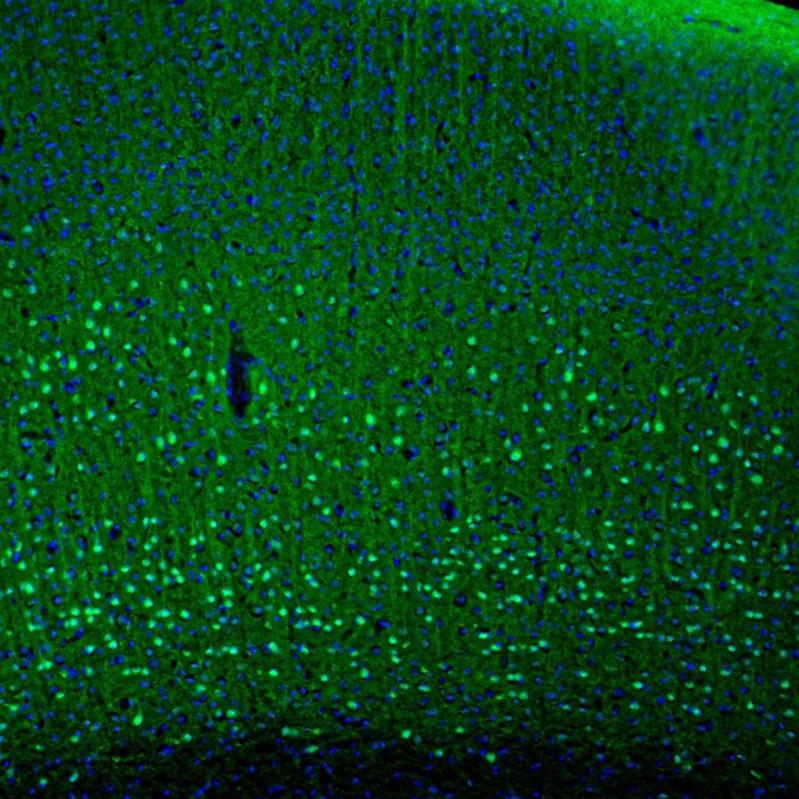

Immunohistochemistry analysis in human cerebral cortex and liver tissues using HPA005792 antibody. Corresponding PCP4 RNA-seq data are presented for the same tissues.